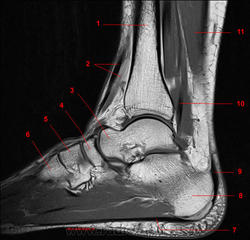

Рис. 14

1, Длинный разгибатель пальцев. 2, Б/берцовая кость. 3, Кубовидная кость. 4, Четвёртая плюсневая кость. 5, Короткий сгибатель пальцев. 6, Сухожилие длинной малоберцовой мышцы. 7, Мышца, отводящая мизинец стопы. 8, Пяточная кость. 9, Малоберцовая кость. 10, Длинная малоберцовая мышца.